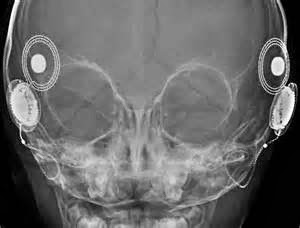

Not MY head.  I only have ONE implant.

Just before I left on vacation with my sons, I visited my surgeon’s office for my one-month, post-activation, check-up.  Aside from the fact that I was already wearing my cochlear implant, it was almost exactly the same as my activation visit one month earlier.  I saw the audiologist, we checked out all the electrodes in my head, tested for the loudest input I could tolerate, and then reprogrammed my devices with those new levels.